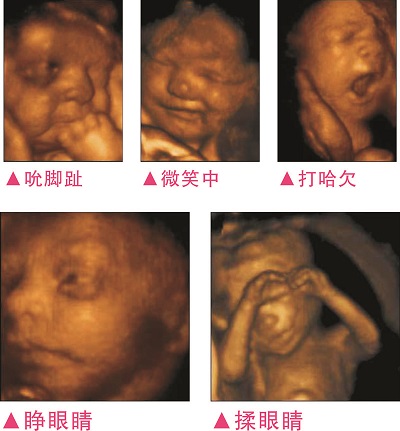

3完整記錄胎兒高清動(dòng)態(tài)寫(xiě)真

四維容積成像技術(shù),智能光源系統展現梯度亮度,渲染畫(huà)面,提高容積成像品質(zhì),高清顯示腹中寶寶的實(shí)時(shí)動(dòng)態(tài)影像,完整記錄寶寶的一舉一動(dòng),讓準爸媽與寶寶Di一次幸福“見(jiàn)面”,更可刻錄成高清視頻,送給未來(lái)寶寶的珍貴禮物。